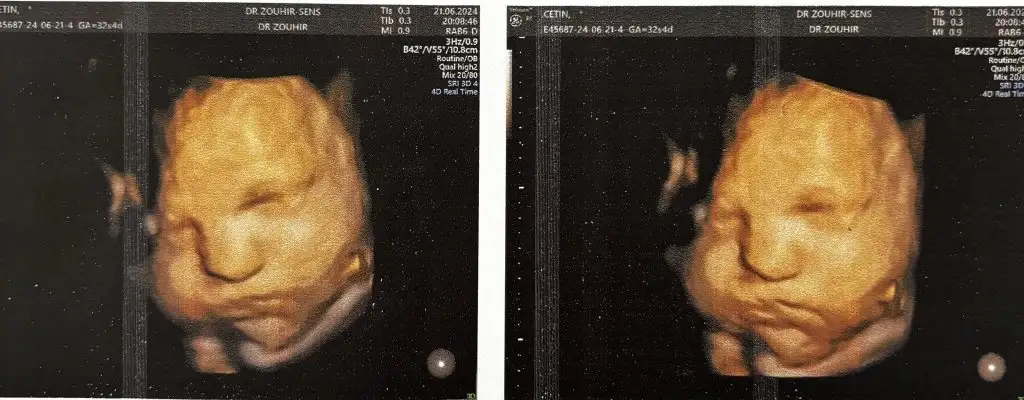

Maşallah kuzuyaEki Görüntüle 3442787

Selam teyzelerii bugün kontrolümüz vardı 32+4 haftalığız, kilomuzda 2360 grammış doğumunda temmuz sonu olur dedi doktoroysaki tahmini doğum tarihi 12-15 ağustos gibiydi